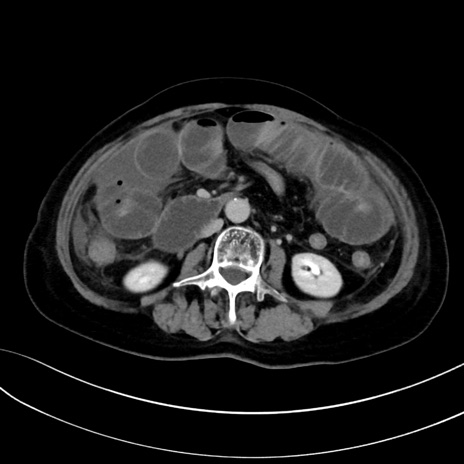

症例13 CT(横断像)1日半後